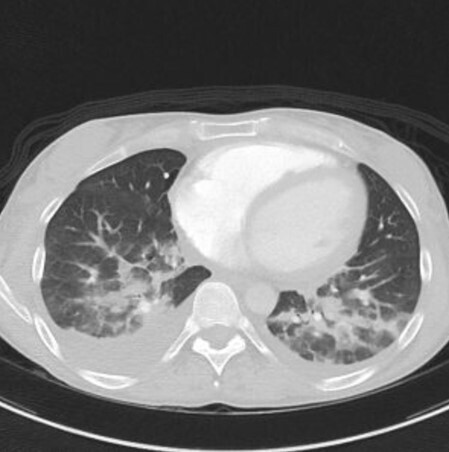

Lors de cette surveillance échographique, une image nodulaire du dôme hépatique apparaît. Le scanner ci-dessous est réalisé pour caractériser cette lésion.

Question 8 - Les caractéristiques sémiologiques de cette lésion sont :

La lésion est hypodense sans injection, mais de densité plus élevée que la graisse sous-cutanée qui apparait presque noire ici (NB : le CHC graisseux est une entité qui existe mais rare).

Le temps artériel se reconnait grâce à la densité importante des artères (par exemple l’aorte).

On parle d’hyperdensité en scanner et d’intensité en IRM.

Un envahissement tumoral vasculaire se manifesterait sous la forme d’une plage infiltrante hypervasculaire au temps artériel au sein de la veine.

Lésion nodulaire typique de carcinome hépatocellulaire (CHC) en scanner : nodule bien délimité hypodense sans injection, hypervasculaire au temps artériel (« wash-in »), présentant un lavage au temps portal et tardif (« wash-out »), et une capsule (dont la définition est la présence d’une couronne se rehaussant au temps tardif).

Un scanner réalisé pour caractérisation d’une lésion hépatique doit comprendre une phase sans injection, une phase artérielle, une portale et une tardive à 3 minutes. Un scanner thoracique pourra également être réalisé dans le bilan d’extension du CHC.

L’imagerie est donc évocatrice de carcinome hépatocellulaire (CHC).